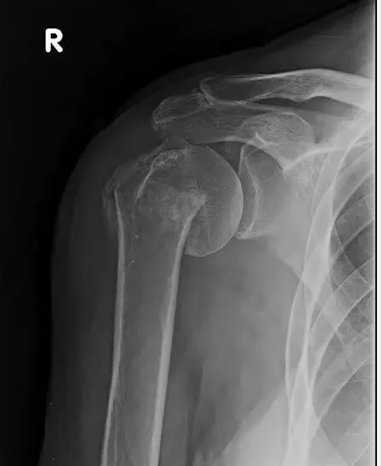

Στην περιοχή του ώμου μπορεί να συμβούν μετά από τραυματισμό κατάγματα του άνω τριτημορίου του βραχιονίου, κατάγματα της ωμοπλάτης και κατάγματα της κλείδας.

Τα υποκεφαλικά κατάγματα του βραχιονίου είναι συχνά στους ηλικιωμένους αλλά συνήθως είναι απαρεκτόπιστα ή ελάχιστα παρεκτοπισμένα και η συντηρητική θεραπεία τους με απλή ανάρτηση του άκρου και σχετικά γρήγορη κινητοποίηση συνήθως αρκεί. Σε συντριπτικά παρεκτοπισμένα κατάγματα ενδείκνυται χειρουργική αντιμετώπιση η οποία περιλαμβάνει την κλειστή ανάταξη και σταθεροποίηση με κοχλίες, την ανοικτή ανάταξη και εσωτερική οστεοσύνθεση, την ημιαρθροπλαστική, την ολική ή την ανάστροφη αρθροπλαστική.